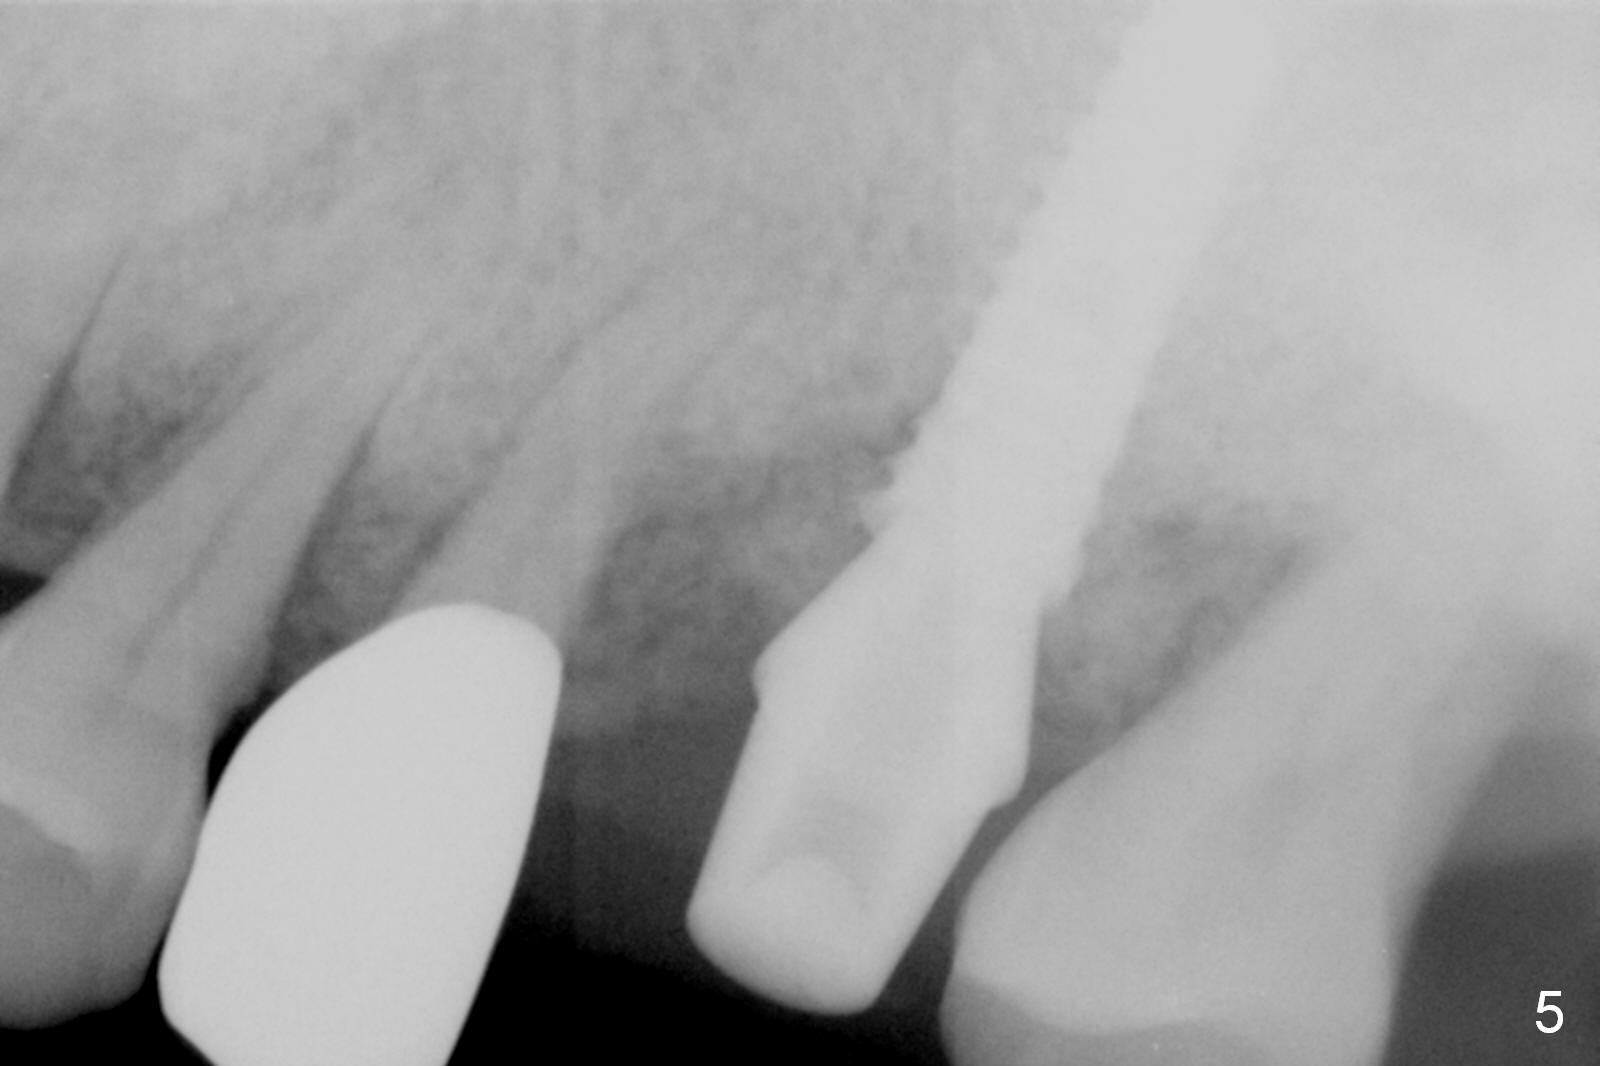

Preop exam show that the tooth #14 appears to be more severe than #18. When the former is extracted with forceps (not so easy), the mesial portion of the mesiobuccal root splits. The latter may be the reason for discomfort and one of the outcomes of advanced peridontitis. The septum is wide enough to use 4.3 mm Magic Drill (MD) following 1.6 mm pilot drill and Marking bur. A 5x13 mm IBS implant is placed apical to the mesial and distal crest and coronal to the septum (Fig.2,3). Insertion torque is ~ 35 Ncm. A 6.0x5.7(4) mm pair abutment is chosen over a 6.5 mm one, because the implant is placed somewhat distally (Fig.4,5). If the implant were placed more apically, the 4 mm cuff would be short for restoration. Allograft and autogenous bone harvested from the MD is placed around the coronal portion of the implant and the abutment cuff (*). Acrylic is spread around the abutment to hold the bone graft in place (without trimming).

The amount of the bone graft mesial and distal the implant seems to reduce 3 and 4 months postop, respectively (Fig.6,7 arrowheads). When the acrylic is cut off 4 months postop, the bone graft is loose. The gingiva is unhealthy. The abutment and implant are loose. A healing abutment is placed (5x4 mm). The implant is torqued to 35 Ncm 6 months postop with the healing abutment reapplied. The patient will return for follow up nearly 9 months postop. A larger healing abutment will be used if the implant is stable. Two weeks later, use a smaller restorative abutment for easy impression. In fact the implant is unstable with #15 mesial shift due to abnormal occlusion with #17 (Fig.8). Bone density around the implant is low (* in Fig.9 (PA), 10,11 (CT sagittal, coronal sections)). A healing screw is placed for self healing. A 2nd option is to remove the implant (Fig.12), BEB (Fig.13) and place the implant deeper (Fig.14) or larger one (5.5-6.5x13 mm). The 3rd option is to place larger and longer implants (Fig.15 (tapered), 16 (cylindrical)). The implant access has partially closed 14 months postop, but there is a small buccal opening with sanguine exudate. Incision reveals severe bone loss around the implant; the mobile tooth #15 is extracted (Fig.17). After debridement and irrigation with normal saline, Vera Graft (Fig.18 *) and Collagen plug are placed with periodontal dressing.